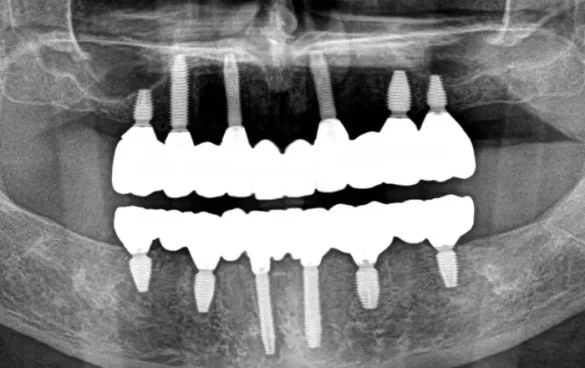

These implants are widely used in restoring the edentulous maxilla and mandible, providing support for removable dentures, fixed bridges, or as single-tooth replacements. Unlike many other implant systems, KAT Implants have a solid body design, which contributes to their strength and long-term success. Their adaptability allows clinicians to place them in a range of bone qualities, including healed ridges and extraction sites, with the possibility of immediate loading if primary stability is adequate.

Flexibility in Applications: KAT Implants can be used in various clinical situations, including single tooth replacements, multiple splinted implants, and full-arch rehabilitations.

Full-Arch Restorations: Suitable for use in All-on-4 style treatments or similar protocols, offering immediate function and aesthetic rehabilitation.